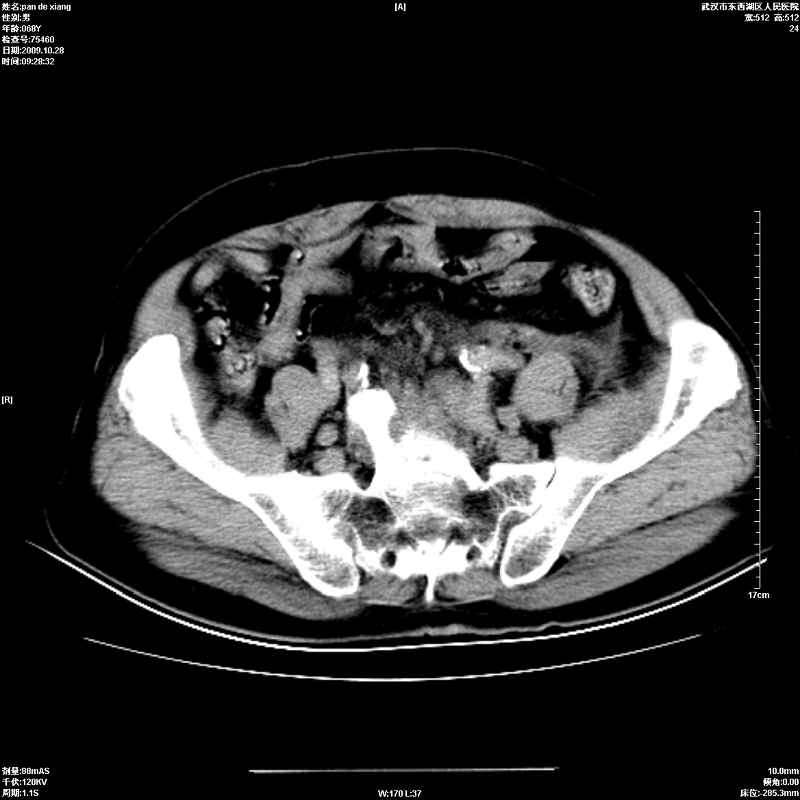

以下是引用杀毒软件在2009-10-28 20:41:00的发言:[br]结合临床考虑---白血病双肾改变或淋巴瘤。

以下是引用zxl51642在2009-10-29 9:59:00的发言:[br]结合临床“单克隆免疫球蛋白血症”,考虑双肾为继发损害并肾功能不全(尿中大量igg及少量iga、igm等大分子免疫球蛋白滤出所致继发损害),椎前软组织肿块为髓外造血。与浆细胞瘤有区别,平扫时有战友说的很清楚。